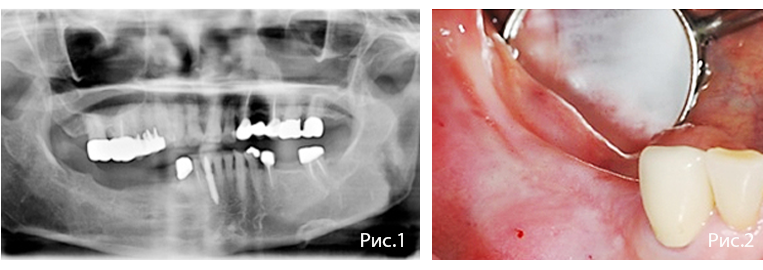

Рис. 11—14. Второе хирургическое вмешательство через 12 недель после имплантации.

Рис. 15—16. Окончательное протезирование через 14 недель после имплантации. Отмечают благоприятное состояние мягких тканей в области вмешательства. Через один год уровень краевой кости и костная поддержка имплантатов стабильны.